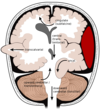

2

3

4